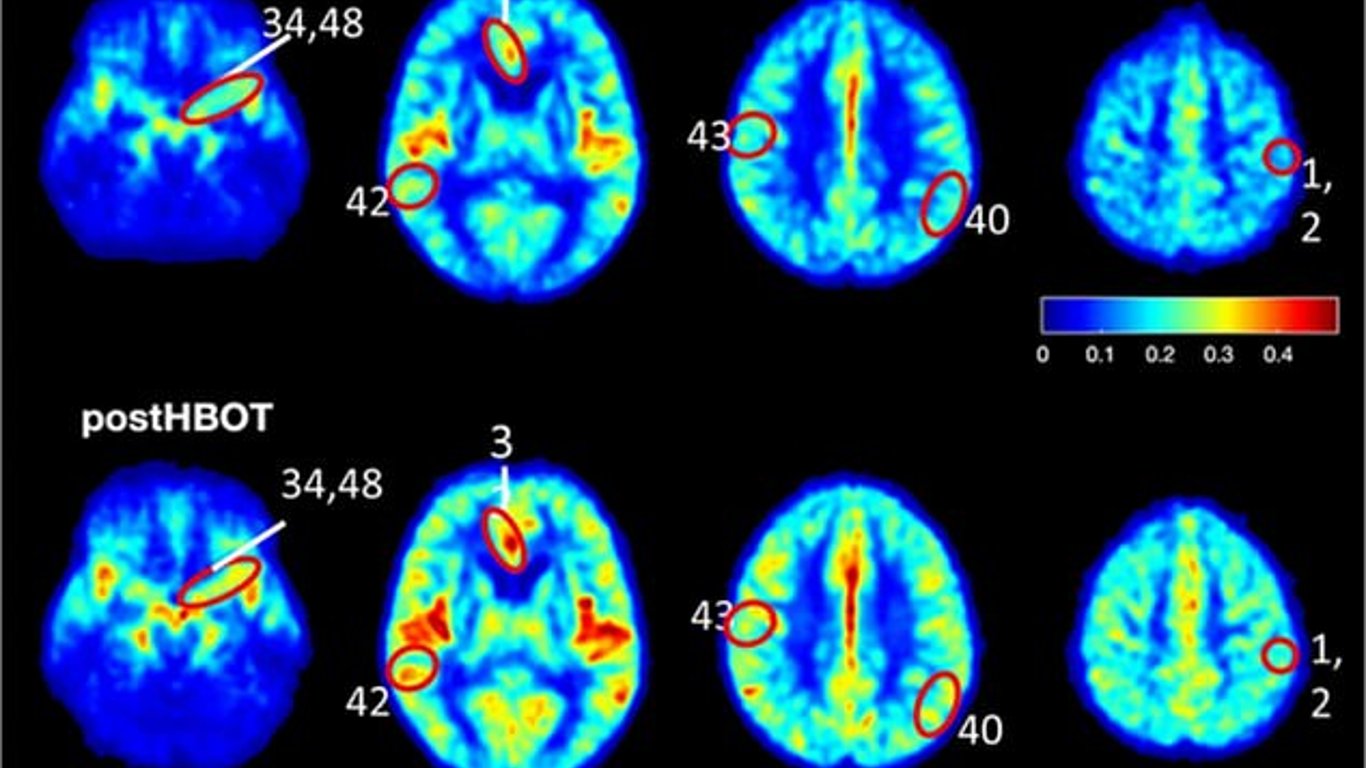

Після тримісячного курсу лікування гіпербаричною кисневою терапією. Кровотік в мозку учасників експерименту покращився на 20 %, пам'ять – на 16,5 %. В ході експерименту люди поміщалися в спеціальні камери з підвищеним тиском.